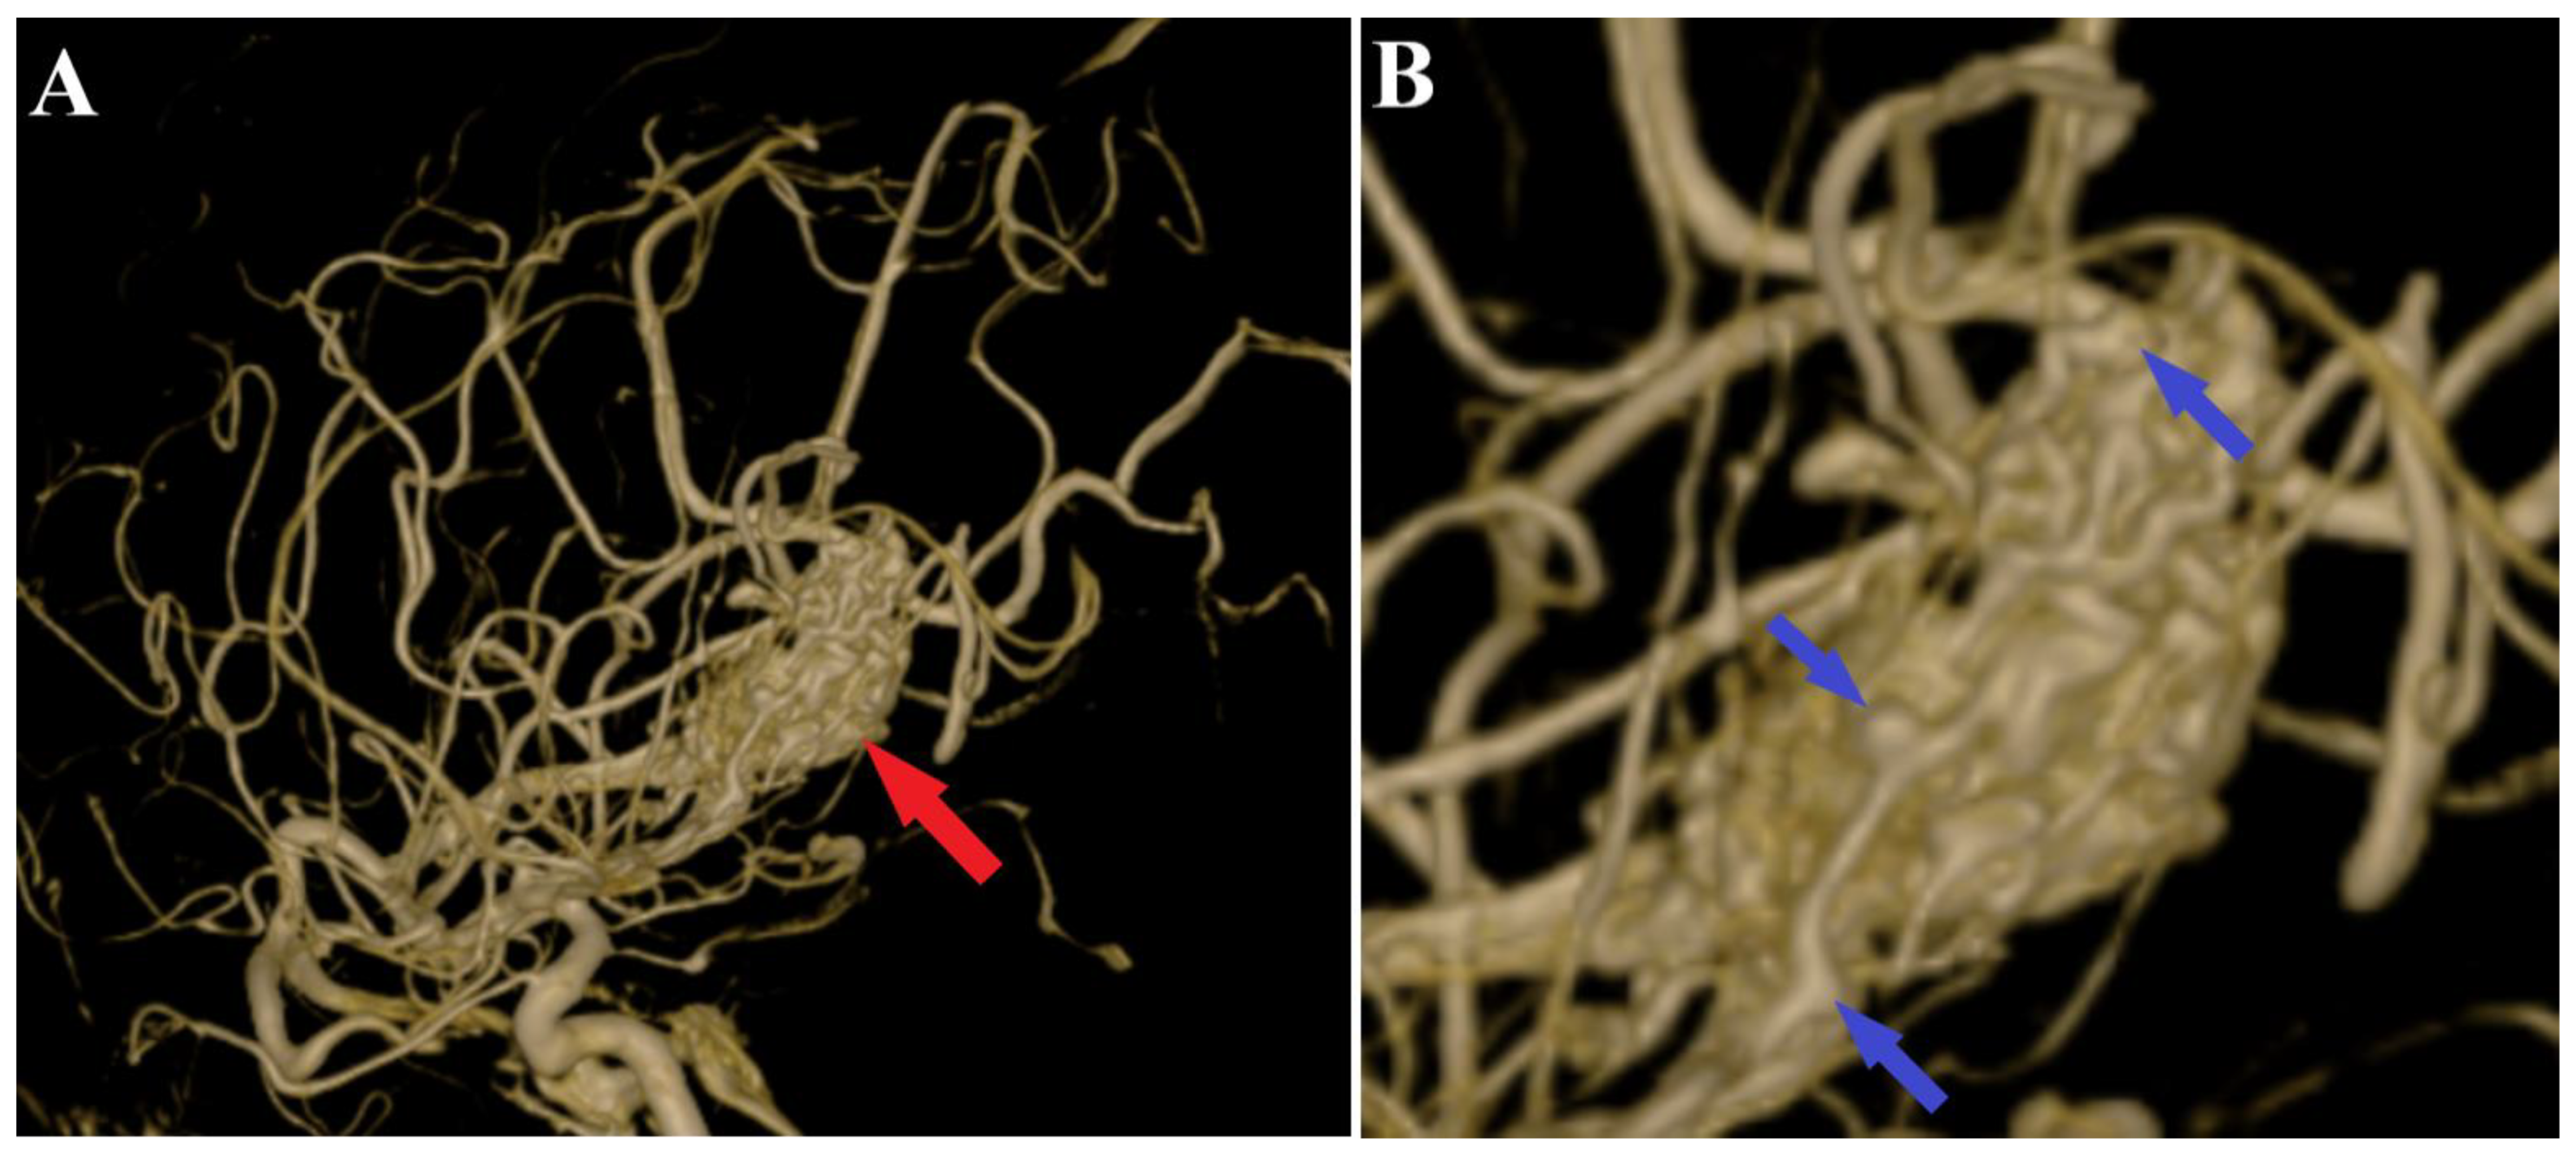

A 44-year-old patient was admitted to our clinic for sudden left hemiparesis MRC 1/5 occurring in the apparent health status 48 h prior to admission, followed by the deterioration of consciousness that become gradually worse, with the patient becoming comatose. She was admitted to our clinic with GCS = 7 points (eye response—2 points, verbal response—2 points, motor response—3 points), orotracheally intubated, and mechanically ventilated. Neurological examination on admission revealed a left hemiparesis, predominantly in the brachial region and comatose state. A brain non-contrast CT scan revealed a voluminous right fronto-temporal intraparenchymal hematoma with panventricular infiltration, significant mass effect on the right lateral ventricle, and 1.5 cm displacement of the midline. Otherwise, normal cerebroventricular CT appearance was seen (Figure 1). Angiography was performed through the selective injection of the internal carotid artery bilaterally, right external carotid artery, and left vertebral artery. Right temporal arteriovenous malformation with arterial afferents from the right anterior choroidal artery and right-sided middle cerebral artery was observed, Spetzler Martin grade III (Figure 2). A nidus of approximately 2/1 cm in size with several intranidal aneurysms was also observed (Figure 3). A single vein was draining into the right cavernous sinus, through an intermediate venous source.

Figure 3.

Preoperative 3D DSA rotational angiography. The 3D reconstruction of rotational DSA (A) depicts the tridimensional topography of the arteriovenous malformation (red arrows). In high-resolution image (B), multiple intranidal sacullar and fusiform aneurysms were found (blue arrows).